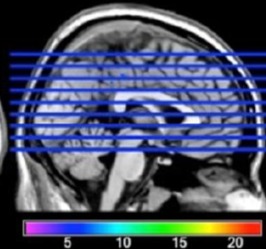

This project aims to elucidate 1) the neural networks for the orthographic, phonological and semantic constituents of Chinese and English reading, 2) how language learning experience shapes the brain structure and functions, and 3) the cognitive functions subserved by the left middle frontal region (LMFG) that are pertinent to reading. Our previous studies published in Nature, PNAS and Current Biology revealed significant variation between the neural substrates of impaired reading in Chinese and English. A central finding was that Chinese dyslexics had reduced activation relative to controls in the left middle frontal gyrus (LMFG) during reading processing but the two groups did not differ in the left temporoparietal region, which has been found deficient in alphabetic dyslexics and is believed to be responsible for rule-based phonological processing. We speculate that the LMFG may be responsible for the mapping of orthography-to-phonology and orthography-to-semantics and the coordination and integration of visuospatial information with linguistic (phonology and meaning) information.

This project aims to analyze lesion-behavior mapping in Chinese aphasic patients using anatomical, diffusion and resting-state functional magnetic resonance imaging. Chinese neurosurgeons used to follow the Western practice of protecting Broca’s and Wernicke’s areas during brain surgery based on the assumption that the language network is universal across cultures. Since the publication of our work in 2004, some neurosurgeons have become aware of the unique role of the LMFG in Chinese reading processing and argued that language-specific brain maps should be adopted for better brain surgery planning (e.g., Feng et al., 2006; Shang et al., 2013; Zhang et al., 2008). For example, a group of neurosurgeons at Shanghai’s Huashan Hospital performed awake surgery and intraoperative language mapping on patients with glioma to map their language regions. The neurosurgeons reported that an additional brain area, the LMFG, was unique in Chinese production and that the language maps for Chinese and English are different. Importantly, with the use of this Chinese-specific language map, the incidence of postoperative language disorders had significantly reduced to 4.5% (in their study based on 66 patients) (Wu et al., 2015, HBM). The findings of this project will serve important theoretical and clinical purposes: 1) inform whether the nature and types of aphasia vary across languages, 2) reveal which brain-behavior metrics better correlate with language deficits, and 3) find out the best assessment protocol that can quickly unveil their stroke-induced language deficits.

Cognitive and brain mechanisms underlying typical and atypical language and reading processing

This project aims to 1) examine the cognitive and brain mechanisms underlying normal and atypical language and reading development, 2) study the comorbidity rate of the two types of disorders, and 3) compare the effectiveness of various reading remediation approaches including phonological training approach and other approaches that emphasize on visual, orthographic, working memory or motor skills. We will use a comprehensive battery of tasks including language and reading ability tests, phonological processing, visuo-orthographic skills, working memory functions (visuospatial working memory, phonological working memory, and executive control functions such as selection and switching) and motor skills will be used to measure children’s general language and reading functions. Their brain scans during language and reading processing will be acquired using MRI and fMRI.